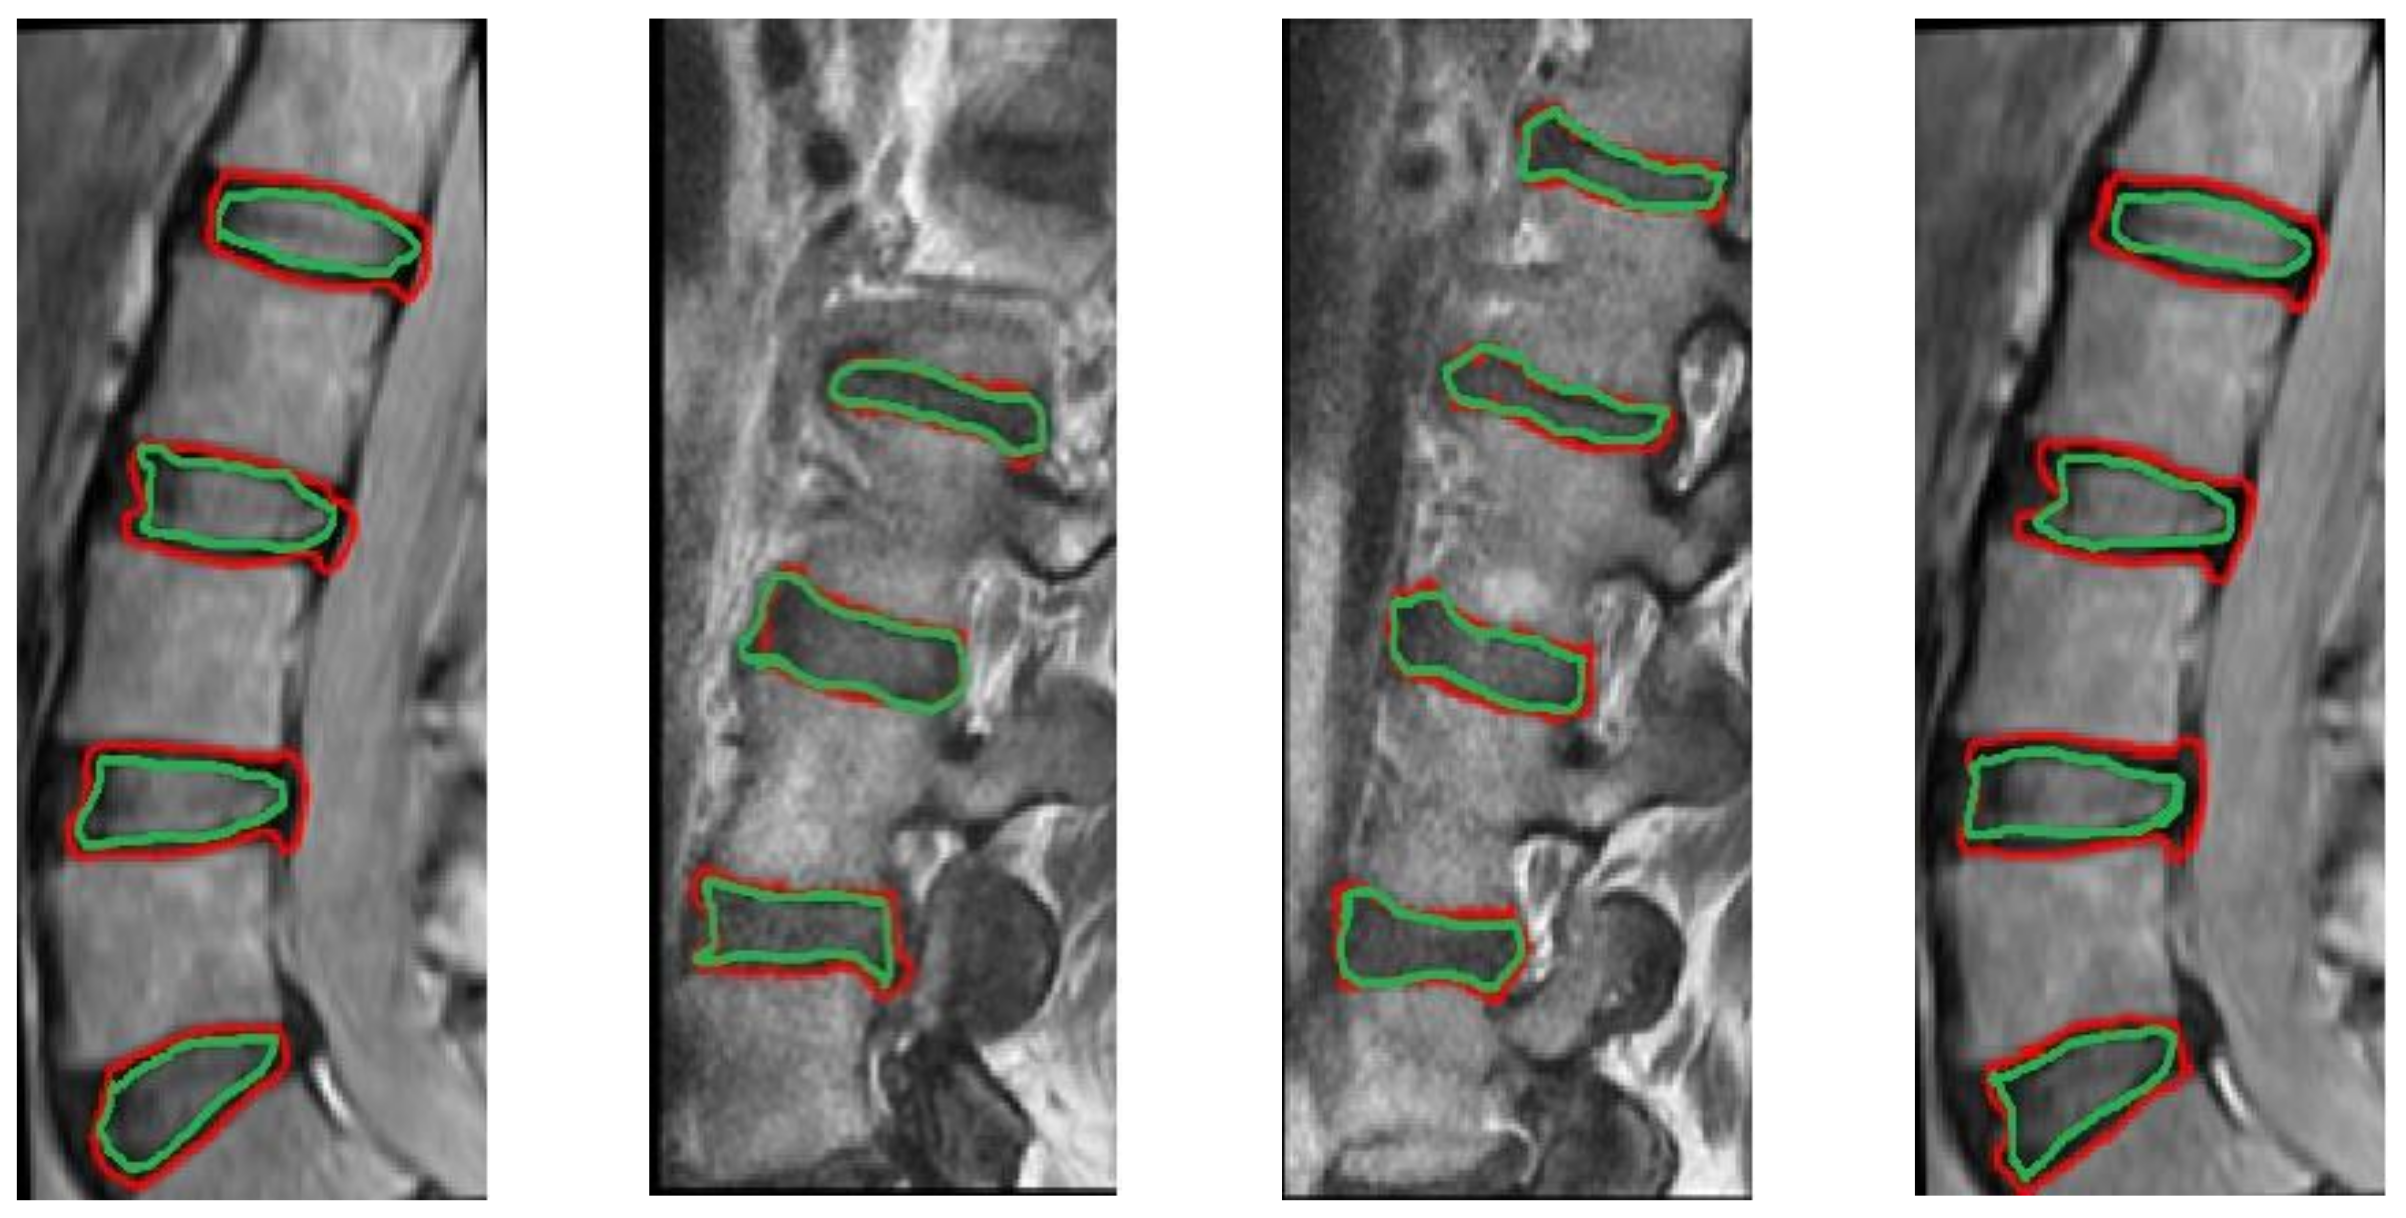

2.5. CT/MRI-Based Segmentation for IVD Boundary Extraction

3.2. Results and Discussion